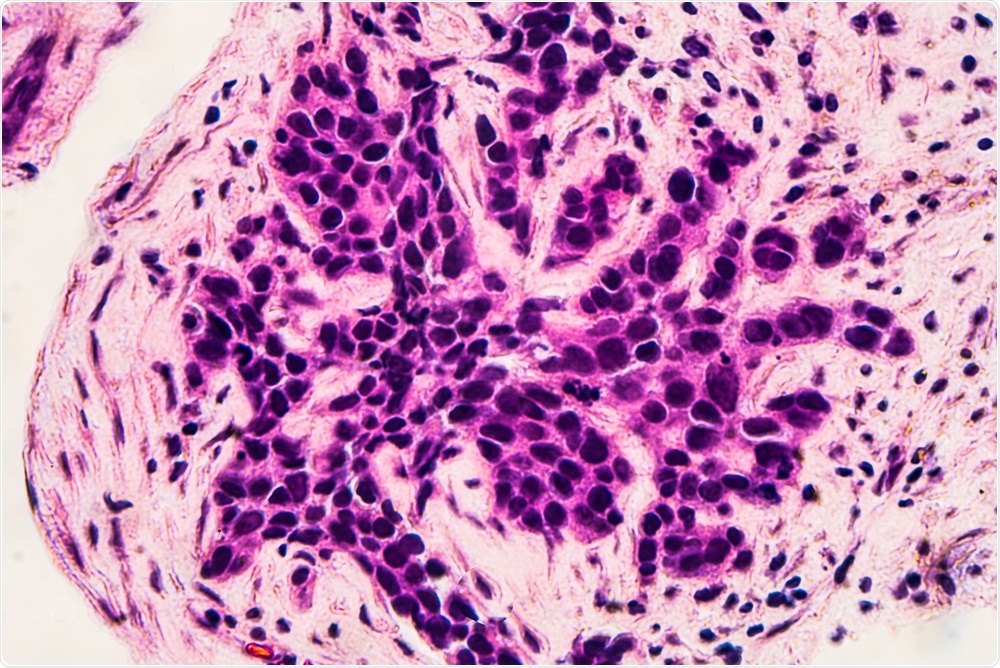

Researchers have developed a targeted therapy that may significantly increase the survival of pre-menopausal women with breast cancer.David Litman | Shutterstock